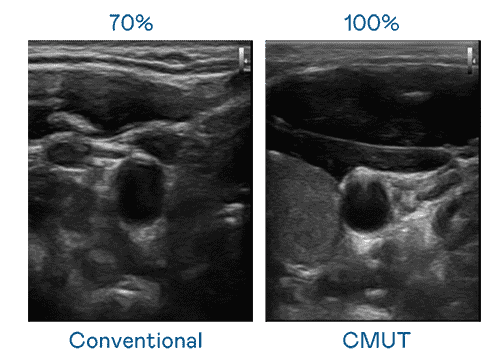

CMUT 技术是一种用电容式微机电元件来产生超音波讯号的技术。。与传统 PZT 压电式技术相比,,,,CMUT 频宽增加 30%,,,更宽频的超音波讯号让影像解析度大幅提升,,,,是实现高影像品质医疗超音波扫描、、、促进精准医疗发展的关键技术。。

大频宽带来超清晰影像

超音波影像的解析度高低,,,首先取决于探头能发出的讯号频宽。。。2121非凡 CMUT 可提供高清晰的超音波讯号,,,,提供高频宽、、、、高灵敏度、、影像纹理细节更高的超音波影像,,,,协助医护人员缩短影像判读时间及利用精准的医疗影像进行诊断。。。